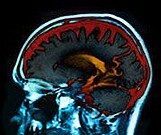

Thalamic Dysconnectivity Seen in Those at Risk for Psychosis

Particularly pronounced among individuals who converted to full-blown illness